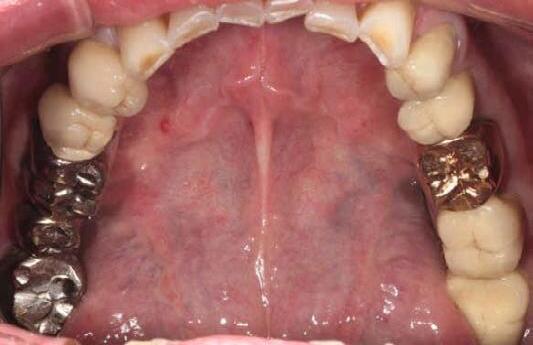

Restoring incisal wear and closing diastema with G-aenial A’CHORD. Courtesy of: Dr Aleksandra Slacan, Poland

Reshaping of teeth and diastema closure with G-aenial A’CHORD. Courtesy of: Dr Andres Silva, Spain